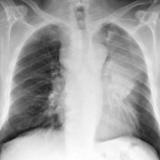

LUL Collapse Case 1 PA

Date: 02/19/2004

Views: 5531